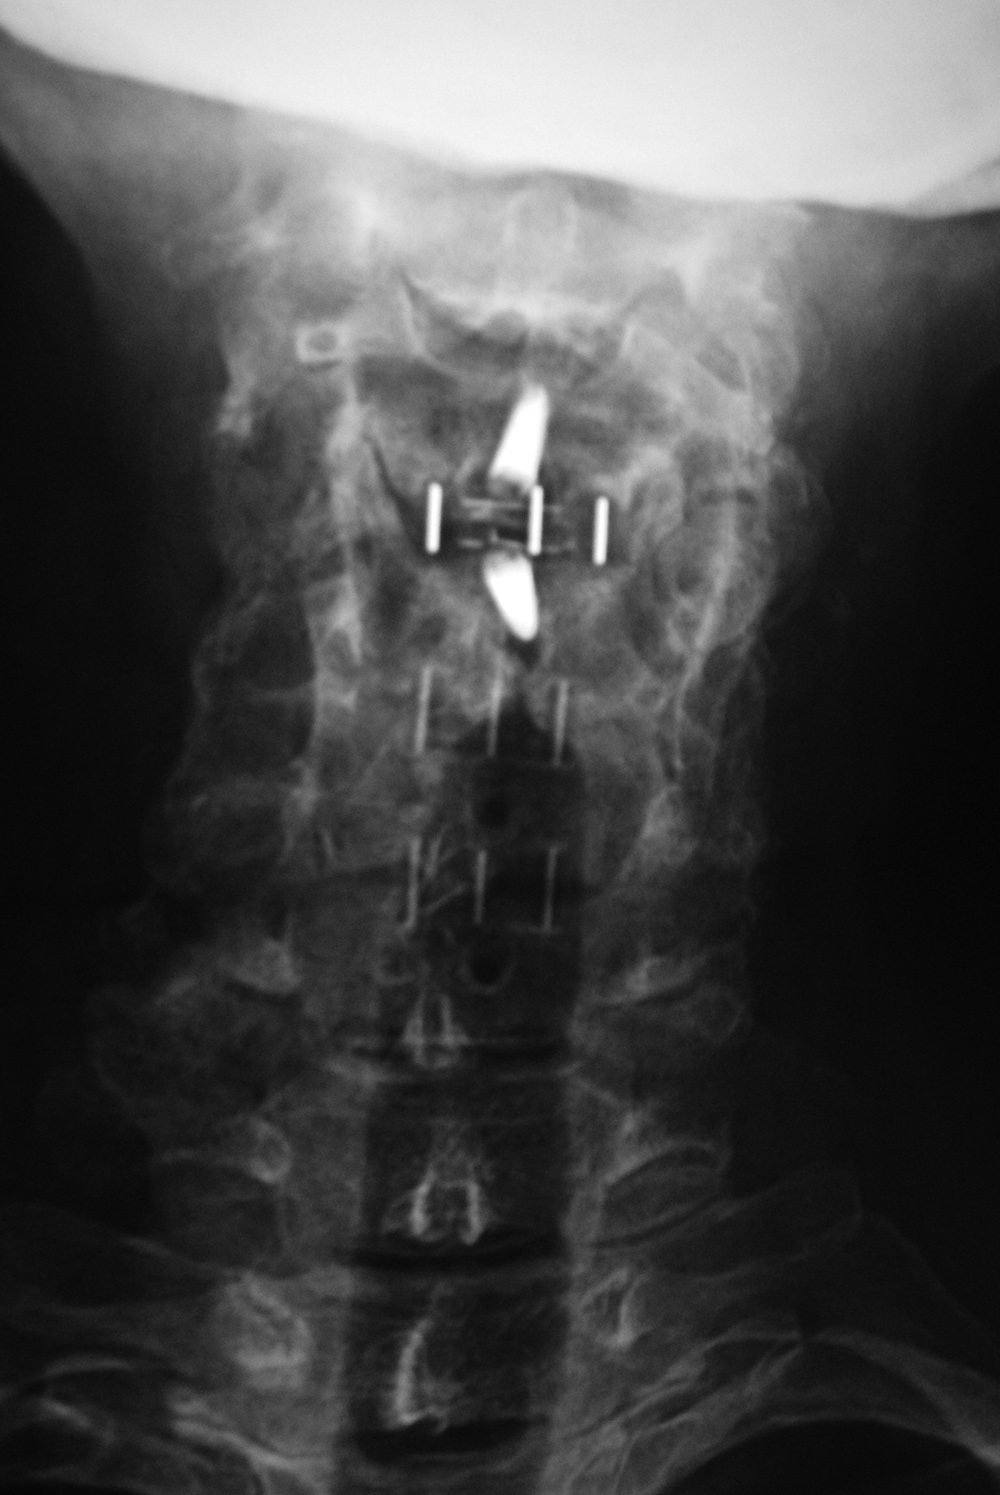

| Odontoid fixation screw AP view |

Odontoid fixation screw lateral view |

Odontoid fracture fixation |

Postoperative lateral radiograph of the cervical spine. There is fixation of an odontoid base fracture by an odontoid screw and a sublaminar wire between C1 and C2. There are also skin staples and a surgical drain in the posterior aspect of the neck |